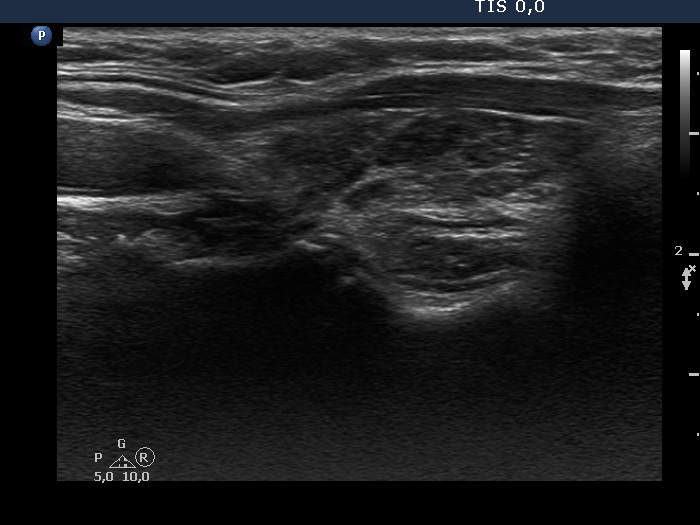

Consecutive patients with the final diagnosis of Hashimoto's thyroiditis - case 58 (1576) (ultrasonographic picture 5)

Left lobe, longitudinal view.